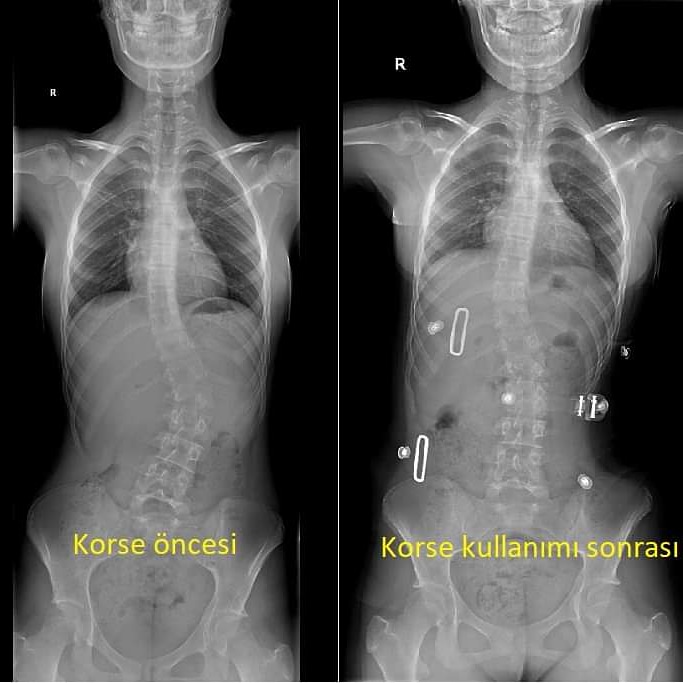

Skolyoz Korsesi Nedir Nasil Takilir Fiyatlari Yapimi Ten Ortopedi

Skolyoz Korse Tedavisi Hakkinda Hersey Prof Dr Murat Bezer Anlatiyor